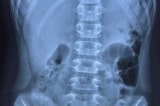

Qua thăm khám, các bác sĩ chẩn đoán ban đầu theo dõi viêm tụy cấp, chưa loại trừ thủng dạ dày tá tràng. Bệnh nhân được đặt thông dạ dày và đề nghị chụp CT-Scan bụng có cản quang. Kết quả CT-Scan có thâm nhiễm mỡ ¼ bụng dưới phải, nghi ngờ chưa rõ là khí trung thất hay thoát vị dạ dày.

Bệnh nhân được nhập lên Khoa Ngoại Tổng Quát theo dõi và được đề nghị làm thêm các xét nghiệm chẩn đoán: CT-Scan ngực bụng, nội soi dạ dày và chụp dạ dày có thuốc cản quang tan trong nước Xenetic.

Các kết quả trả về: Công thức máu có bạch cầu 22.150/mcl, Neutrophil 88,6%. Nội soi dạ dày: Rách tâm vị thực quản dưới nham nhở, diện rách rộng, gồ cao, đáy sâu chưa loại trừ thủng bít (CĐPB với u sùi vùng tâm vị). Chụp thực quản dạ dày cản quang không ghi nhận thoát thuốc cản quang ra ngoài.

(Mũi tên trắng: vị trí thủng thực quản, Hình chữ thập trắng: thành thực quản dưới, Hình ngôi sao trằng: vị trí đáy vị đã được kéo xuống sau khi di động thực quản dưới). (Ảnh: benhvien115.com.vn)